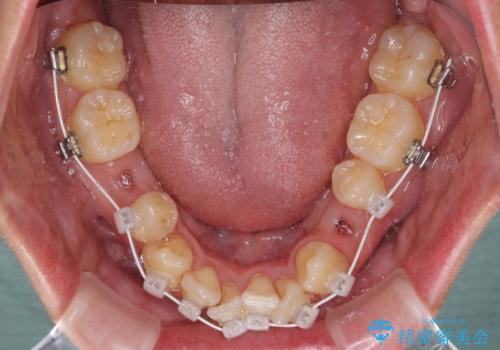

叢生が著しいため、上下左右の小臼歯4本を抜去し、目立たないワイヤー装置にて矯正治療を行うこととしました。

下顎の歯列全体が右側にずれているため、右下のみ第二小臼歯を抜歯し、上顎は補助装置を使用して、極力上下の正中を合う位置にて咬み合わせを改善するようにしました。